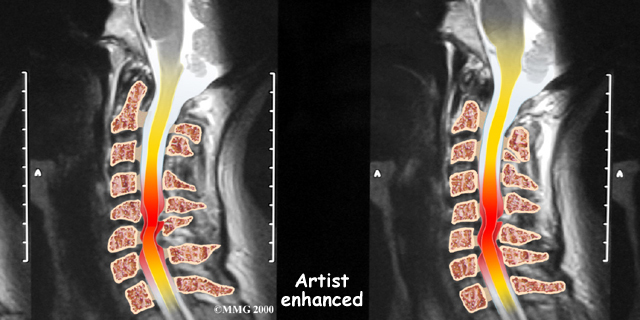

If more information is needed, your doctor may order a magnetic resonance imaging (MRI) scan. The MRI machine uses magnetic waves rather than X-rays to show the of the body. This test gives a clear picture of the spinal cord and can show where it is being squeezed. This machine creates pictures that look like slices of the area your doctor is interested in. The test does not require any special dye or a needle.

A computed tomography (CT) scan may also be ordered. The CT scan is a detailed X-ray that lets doctors see slices of bone tissue. The image can show if bone spurs are protruding into the spinal column and taking up space around the spinal cord.

The bony spinal canal normally has more than enough room for the spinal cord. Typically, the canal is 17 to 18 millimeters around, slightly less than the size of a penny. Spinal stenosis occurs when the canal narrows to 13 millimeters or less. When the size drops to 10 millimeters, severe symptoms of myelopathy occur. Myelopathy is a term for any condition that affects the spinal cord. The symptoms of myelopathy result from pressure against the spinal cord and reduced blood supply in the spinal cord as a result of the pressure.

Degeneration is the most common cause of spinal stenosis. Wear and tear on the spine from aging and from repeated stress and strain can cause many problems in the cervical spine. The intervertebral disc can begin to collapse, shrinking the space between vertebrae. Bone spurs may form that protrude into the spinal canal and reduce the space available to the spinal cord. The ligaments that hold the vertebrae together may become thicker and can also push into the spinal canal. All of these conditions .